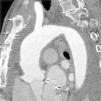

Uma vez que a cintigrafia com marcação de leucócitos sugeria que o processo infecioso se limitava ao 1/3 distal do corpo do esterno, foi tentado tratamento conservador com antibioticoterapia e drenagem. A doente desenvolveu síndrome da veia cava superior pelo que repetiu angioTC revelou «pseudoaneurisma gigante, em rotura contida e fazendo corpo com o esterno» (Figura 3).